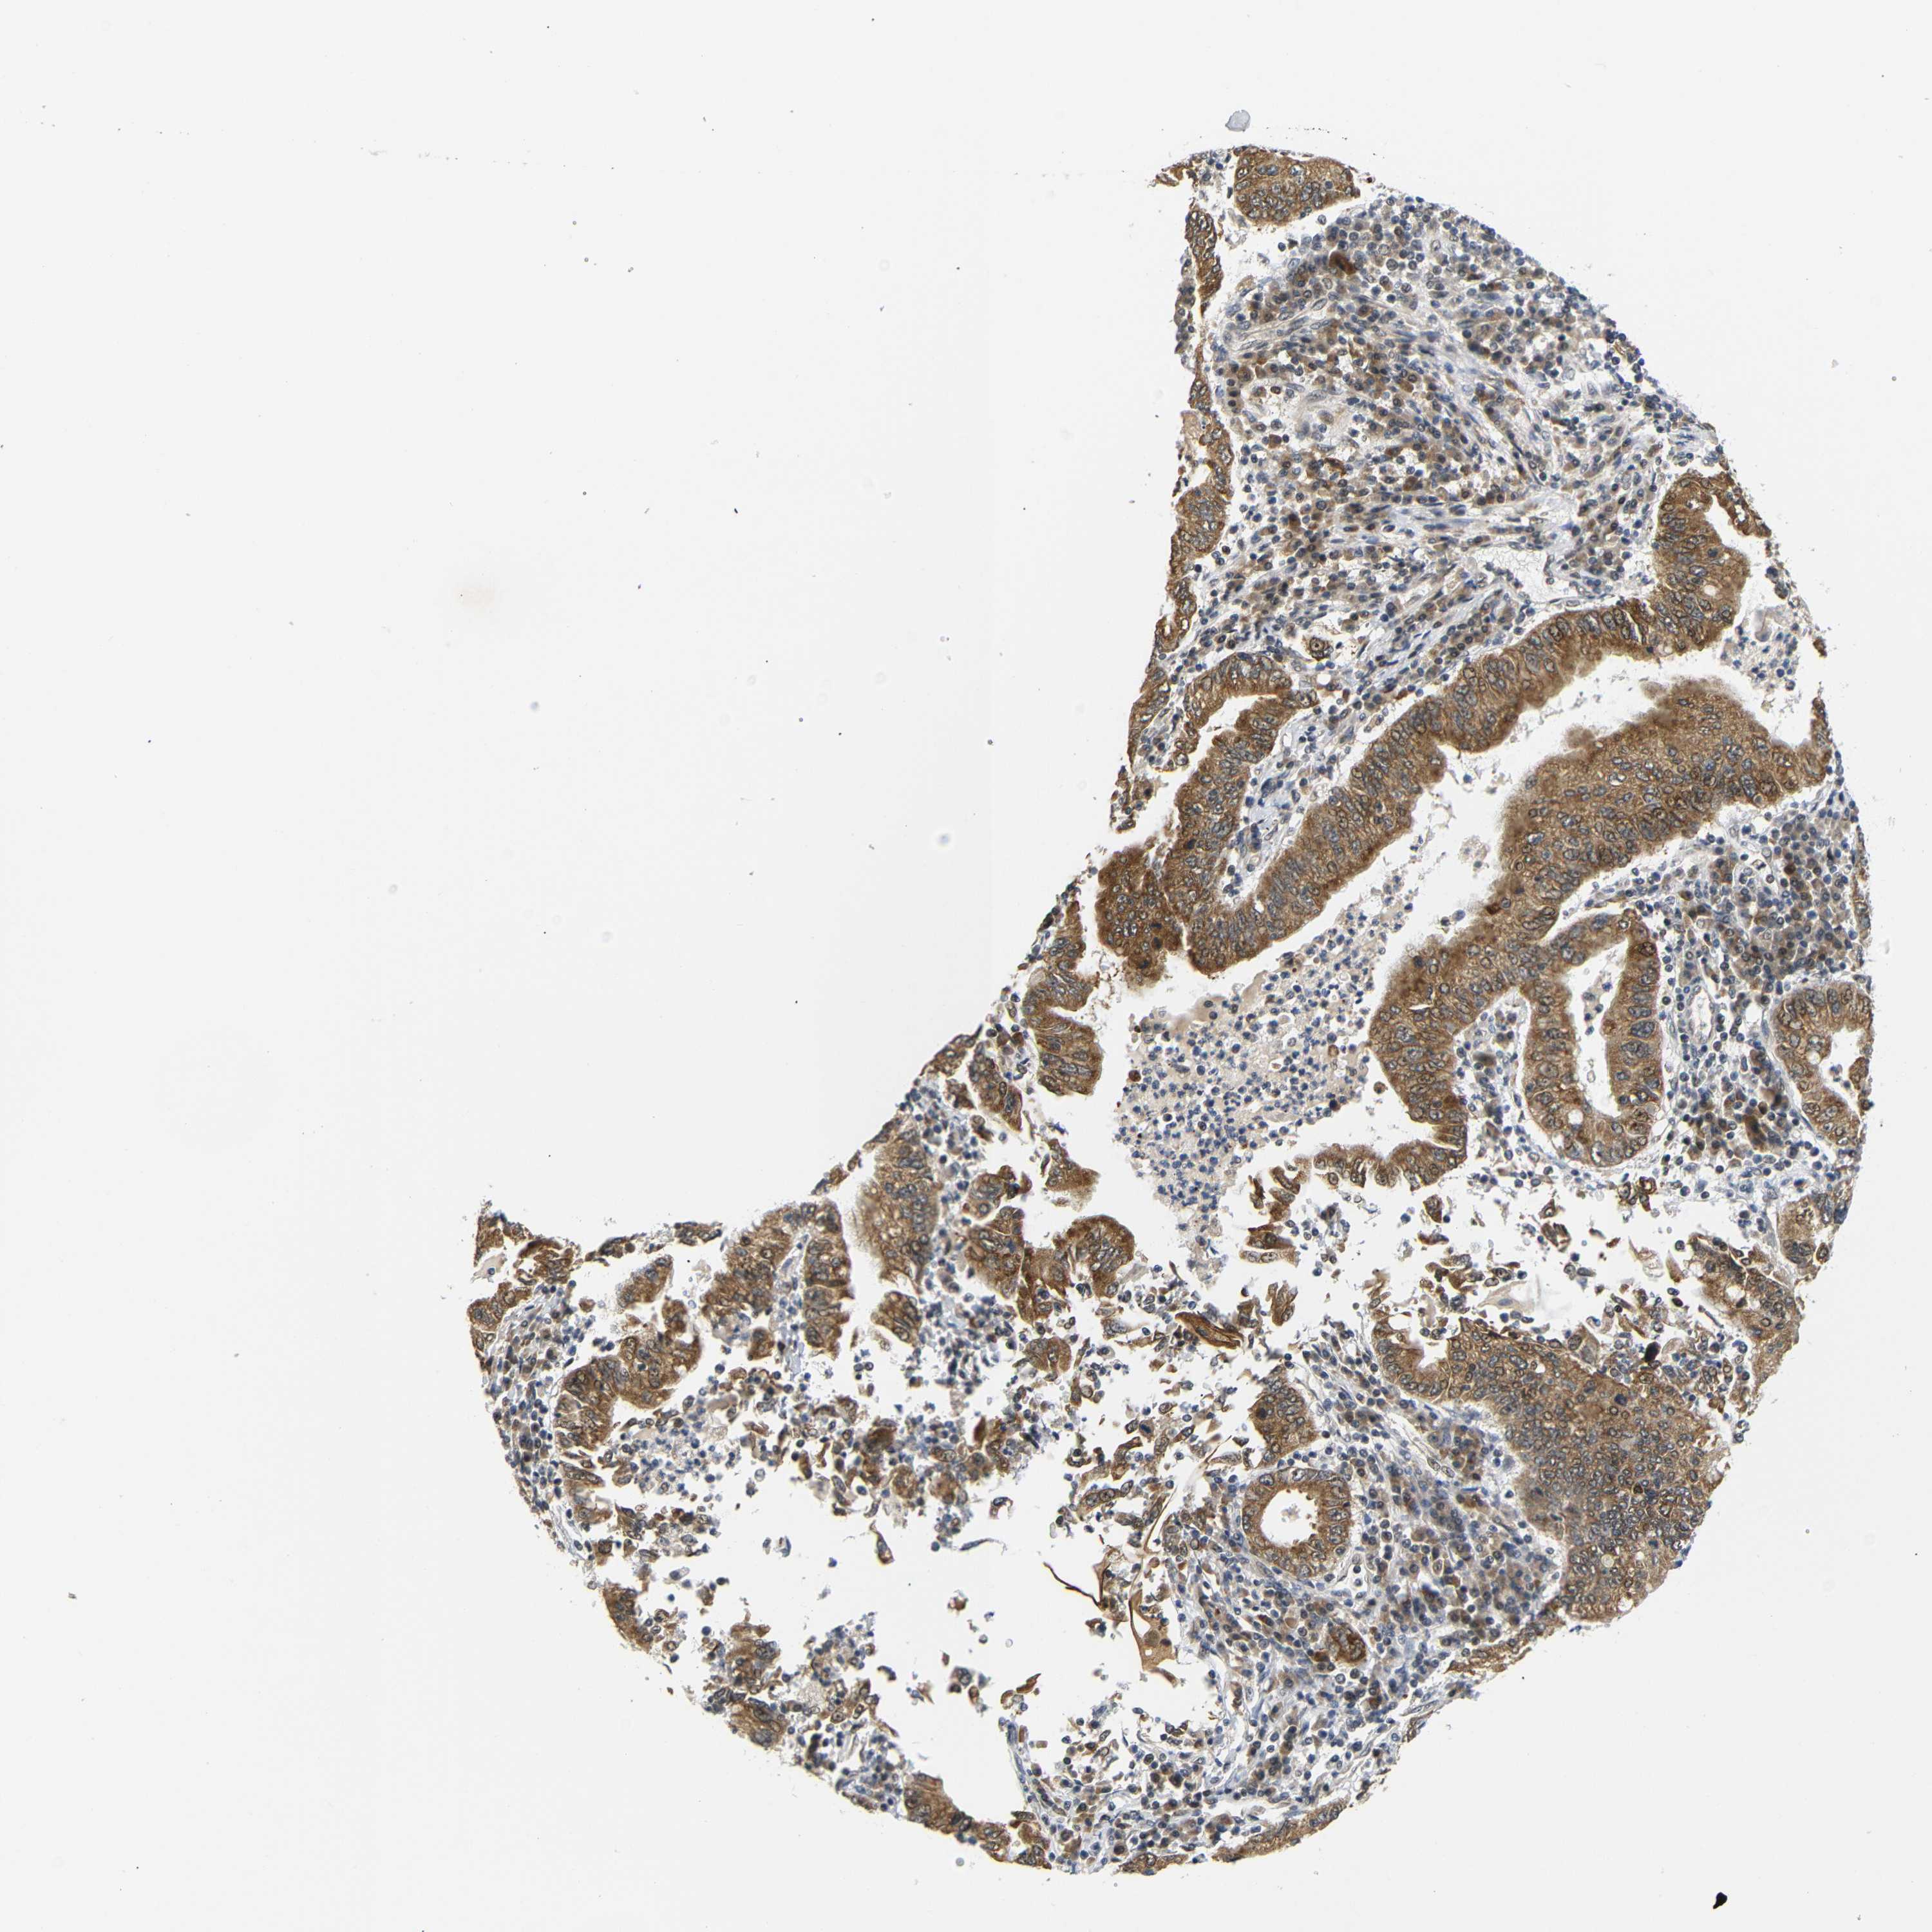

STOMACH CANCER - Protein expressioni

A mouse-over function shows sample information and annotation data. Click on an image to view it in a full screen mode. Samples can be filtered based on level of antibody staining by selecting one or several of the following categories: high, medium, low and not detected. The assay and annotation is described here.

Antibody stainingi

Antibody staining in the annotated cell types in the current human tissue is reported as not detected, low, medium, or high, based on conventional immunohistochemistry profiling in selected tissues. This score is based on the combination of the staining intensity and fraction of stained cells.

Each image is clickable and will lead to virtual microscopy that enables deeper exploration of all samples and also displays staining intensity scores, fraction scores and subcellular localization as well as patient and tissue information for each sample.

Antibody HPA071370

Antibody CAB013080

Staining

High

Medium

Low

Not detected

Intensity

Strong

Moderate

Weak

Negative

Quantity

>75%

75%-25%

<25%

None

Location

Nuclear

Cytoplasmic/membranous

Cytoplasmic/membranous,nuclear

Adenocarcinoma, NOS

Adenocarcinoma, High grade